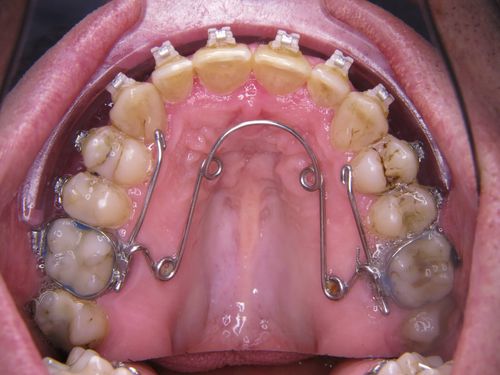

Häufig stellt sich heraus, dass die Kiefer in der Breite zu schmal sind. Insbesondere im Oberkiefer ist dies nicht selten. Als Behandlungsziel ist dann die Verbreiterung des Oberkiefers kausal zielführend und nicht die Entfernung von Oberkieferzähnen, denn der Kiefer ist ja zu schmal und nicht die Anzahl der Zähne zu hoch. Die Behandlung erfolgt wie im folgenden Film dargestellt:

In einem ersten Behandlungsschritt wurden Ober und Unterkiefer verbreitert (transversaler Erweiterung). Allein dadurch zeigte sich schon eine Verbesserung der Atmung im Schlaf.